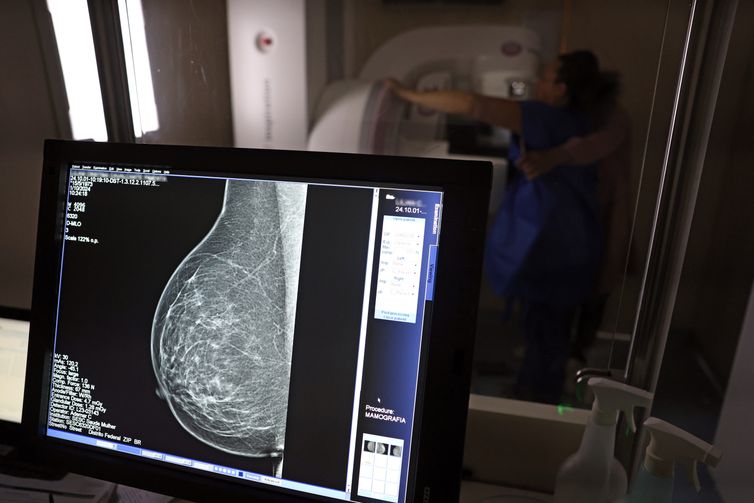

Um dos principais critérios é a realização de rastreamento organizado, ou seja, a convocação das usuárias para realizarem exames regularmente, mesmo sem sintomas. No caso do câncer de mama, a cartilha seguiu o protocolo do Ministério da Saúde e do Instituto Nacional do Câncer (Inca): mamografias a cada dois anos para as mulheres com idades entre 50 e 69 anos.

Teste de mamografia realizado na Campanha Outubro Rosa: Sesc-DF. Foto: José Cruz/Agência Brasil – José Cruz/Agência Brasil